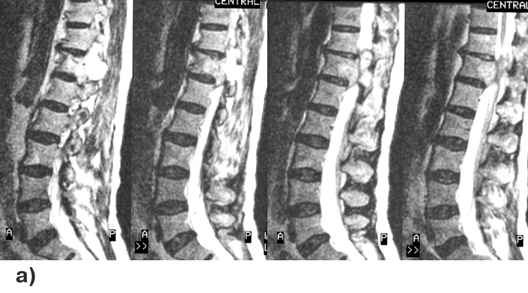

На спондиллограммах, КТ и МРТ (рис. 6) выявляется очаг деструкции в теле или в отростках позвонка с ячеистой структурой по периферии, прилегающей к тонкому ободку — зоне реактивных остеобластических изменений. Со временем выраженность отграничивающих опухоль склеротических изменений кости нарастает, киста отделяется от здоровых участков позвонка и переходит в стадию зрелости (сформированности) процесса. В ранних стадиях заболевания при биопсии из иглы под давлением выходит венозная кровь, из зрелой кисты — серозно-геморрагическая жидкость с различной степенью окрашивания.

Рисунок 6. Аневризматическая костная киста 1 грудного позвонка. МРТ, Т1 и Т2-взвешенные изображения, сагиттальная проекция